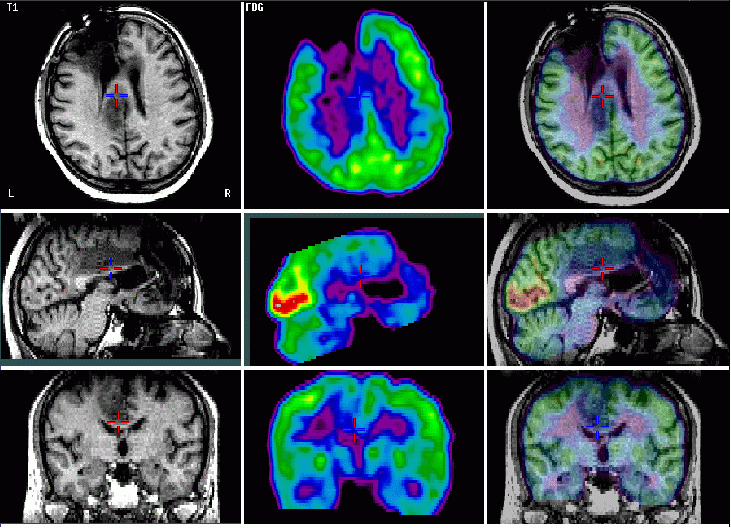

Képfúzió:

Funkcionális és azonos helyzetű strukturális kép együttes

bemutatása

Alacsony malignitású glioma újrafejlődése: [F-18] FDG PET

Az MR-rel az agytumor műtéti eltávolítása után 2 évvel kimutatott középvonali laesio nem dúsítja az FDG –t, ezért alacsony malignitási fokú tumornak, esetleg hegszövetnek tarható: